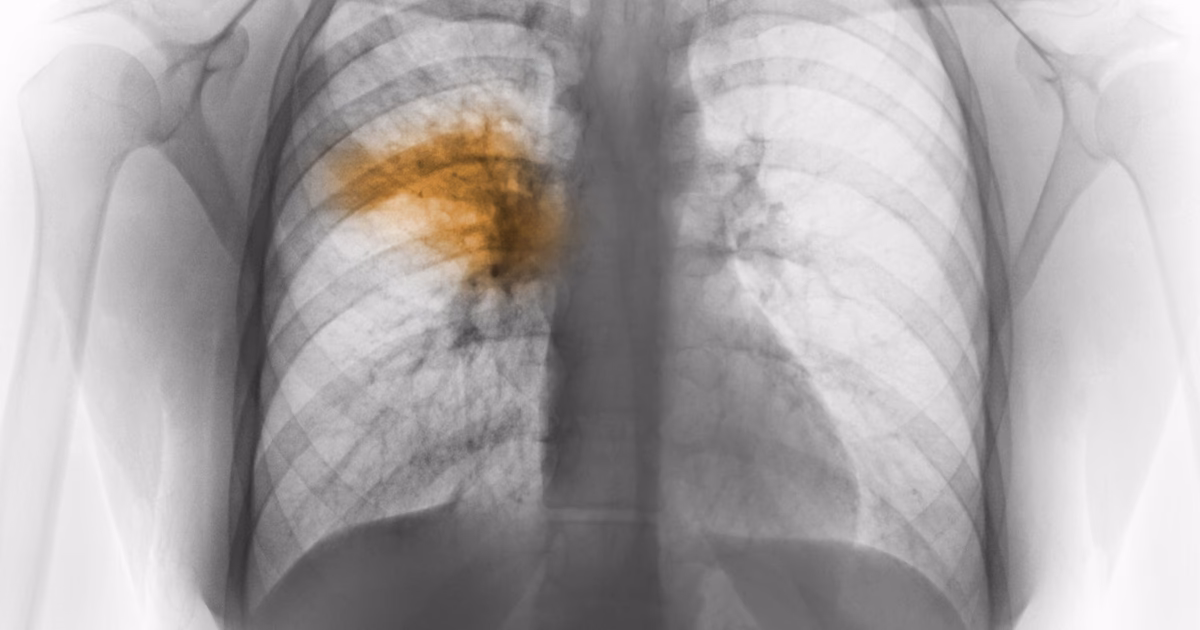

For at stille en korrekt diagnose vil lægen typisk lytte på lungerne med et stetoskop og udføre en række tests. Disse kan omfatte billeddiagnostik som et røntgenbillede af brystkassen eller en CT-scanning for at visualisere infektionen i lungerne. Blodprøver kan også tages for at identificere tegn på infektion og fastslå den underliggende årsag.